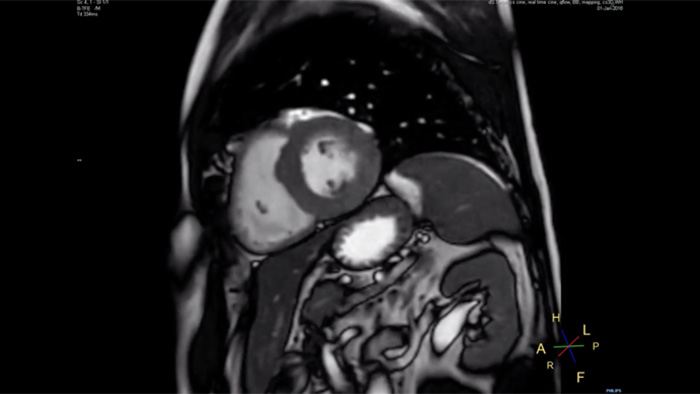

4.8 sec breath hold time

Since short breath hold times make it easier for our patients to comply, the failure of breath holding largely disappeared.

At our facility, we found in Cardiac MR fewer breath holds are now needed, or breath hold times are shortened."

Dr. Takashi Koyama, MD, PhD, Diagnostic Radiologist and Director of the Department of Radiology Center and Diagnostic Radiology, Kurashiki Central Hospital, Japan

A 15- or 16-second breath-hold is tough for many cardiac patients. With Compressed SENSE we actually have protocols now that can get that below 10 seconds. It’s a lot easier to get through for a patient, and patients are a lot more satisfied with the experience.”

Trevor Andrews, Ph.D., MR Physicist, University of Vermont Medical Center, USA